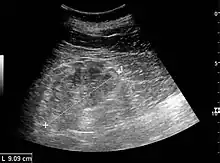

The hydronephrosis is typically graded visually and can be divided into five categories going from a slight expansion of the renal pelvis to end-stage hydronephrosis with cortical thinning (Figure 15). The evaluation of hydronephrosis can also include measures of calyces at the level of the neck in the longitudinal scan plane, of the dilated renal pelvis in the transverse scan plane and the cortical thickness, as explained previously (Figure 16 and Figure 17).[1]

Figure 16. Hydronephrosis with dilated anechoic pelvis and calyces, along with cortical atrophy. The width of a calyx is measured on the US image in the longitudinal scan plane, and illustrated by ‘+’ and a dashed line.[1]